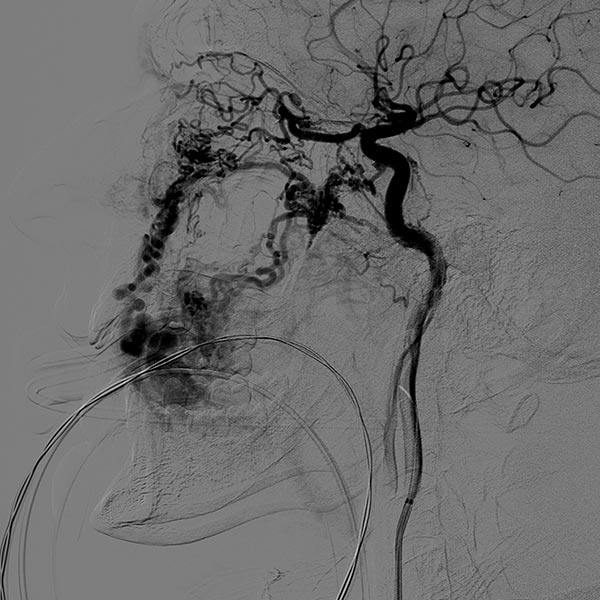

Laterale Ansicht einer digitalen Subtraktionsangiographie nach Injektion in die linke Arteria carotis externa. Die AVM ist als diffuser, netzartiger Nidus mit direktem, starken venösen Abstrom zentral in der linken Wange erkennbar (Fast-flow-Malformation).

Laterale Ansicht, DSA nach Anspritzen der linken Arteria carotis interna. Auch aus der Arteria carotis interna erfolgt eine massive Versorgung des Nidus der AVM, vor allem über die Arteria ophthalmica und den Truncus meningohypophysealis.

Dies erschwert die Embolisationstherapie erheblich.